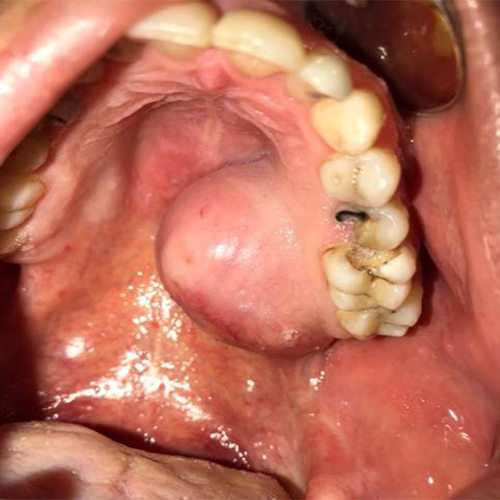

۷) ادنتوژنیک کراتوسیست: در بخش عقب فک پایین شایعتر است (از سن ۱۰ تا سی سالگی بیشتر رخ میدهد). هرگز بدخیم نمیشود اما در طول استخوان می تواند رشد کند و تخریب استخوانی وسیعی ایجاد کند بدون آنکه تورم رخ دهد.۸) آملوبلاستوما: یک تومور خوشخیم است در داخل استخوان فک (به ویژه فک پایین در قسمت عقب) که میتواند تورم مشهود ایجاد کند. این تومور در برخی موارد تهاجمی است و سرعت و شدت تخریب زیادی دارد.

در اولین فرصت به وسیله جراحی باید حذف شود.